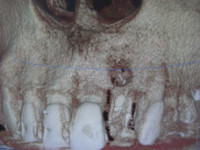

午前のオペ後に右上6番をソケットリフトしてインプラントを埋入された患者様が定期チェックに来院されましたのでご了解の上で画像をアップさせていただきました。

今年で10年経過いたしましたが全く問題なし、快調に噛み込めているとのことでした。プラークコントロールも問題なくこれからもしっかり定期チェックしていきましょう。